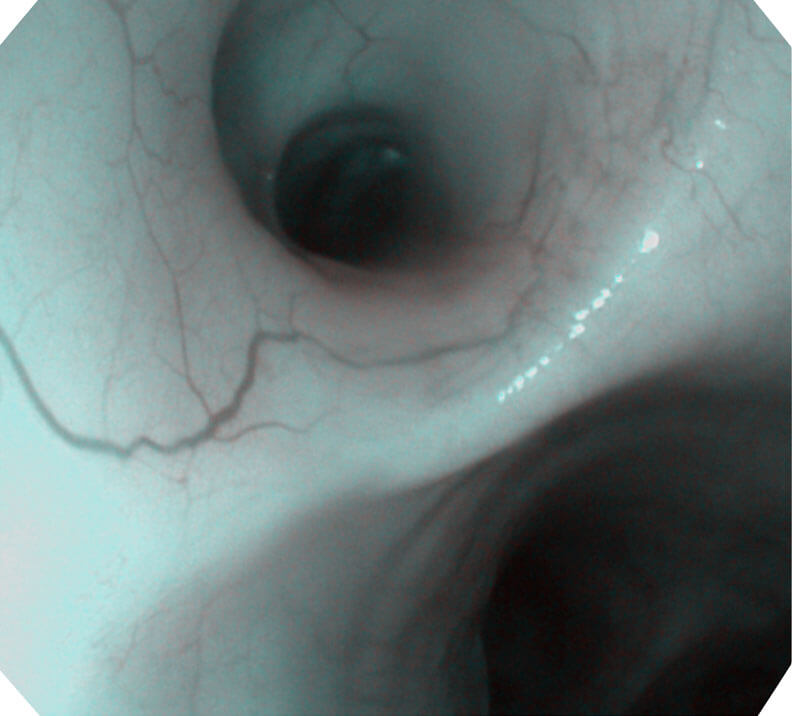

120°视场角,满足更大视野范围的观察。配合 VIST 染色,助力呼吸系统疾病的诊断。

(Versatile Intelligent Staining Technology, VIST)

光电复合染色成像技术(VIST)是一种光学滤波和数字滤波相结合的染色成像技术,摒弃了滤光转轮而直接采用光谱组合的方案,加入了血红蛋白吸收高峰与次高峰的蓝紫光和绿光光谱,更有利于黏膜血管吸收,突显浅表层血管和中层血管的对比度,因而具备更高的图像对比度,有助于观察微细结构变化及病灶边界的观察。